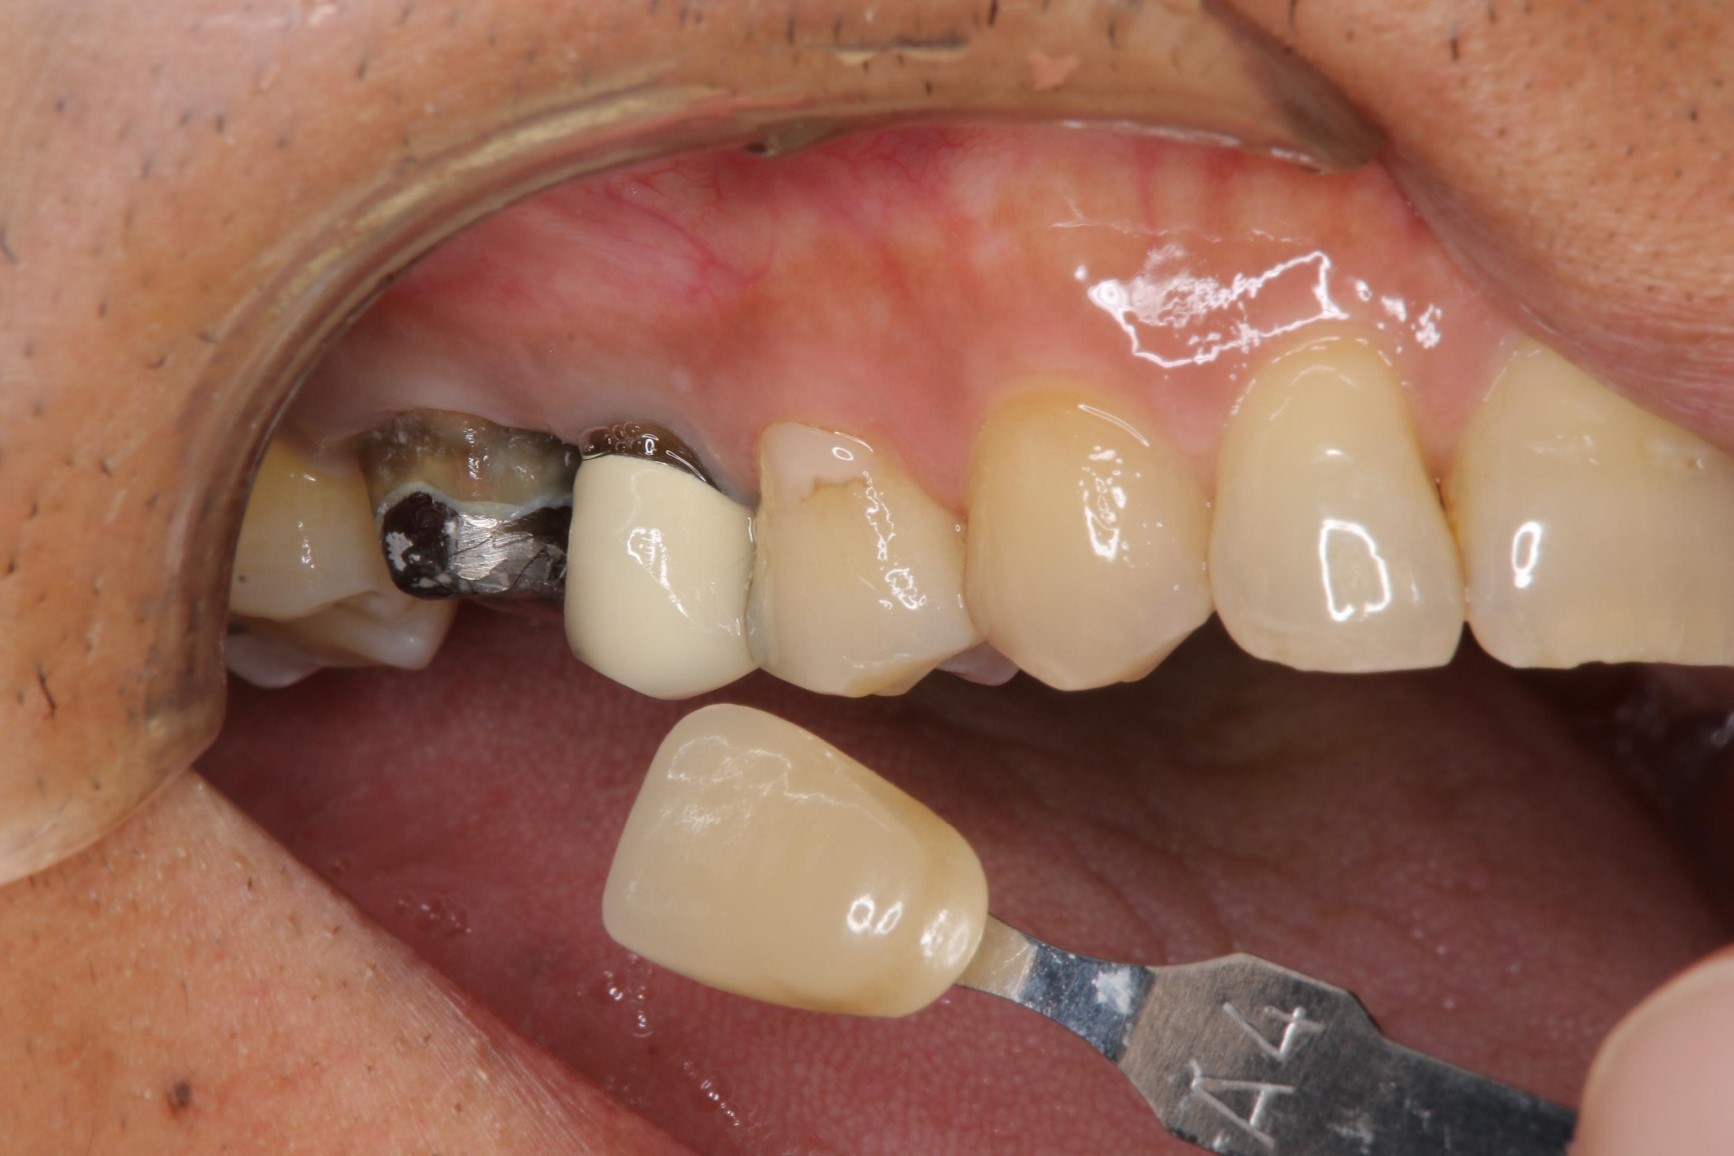

照相比色

上面弓、上咬合器